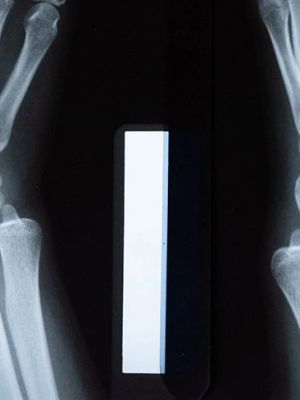

Rendgen RTG nadlaktice, podlaktice

3.500 RSD

RTG nadlaktice se odnosi na rendgenski pregled gornjeg dela ruke, odnosno regiona između ramena i lakta. Snimak može otkriti prelome, dislokacije, tumore ili infekcije u kostima nadlaktice.

RTG podlaktice odnosi se na rendgenski pregled donjeg dela ruke između lakta i ručnog zgloba. Ovaj pregled se koristi za procenu povreda, fraktura i drugih patoloških stanja kostiju podlaktice, uključujući radijus i ulna.